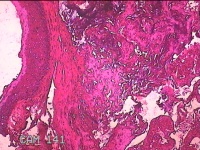

声带新生物

性别

男

年龄

29岁

临床诊断

声带息肉

一般病史

声嘶1月余。

标本名称

声带肿物

大体所见

灰白粉红色小米大组织一块。

良性病变。